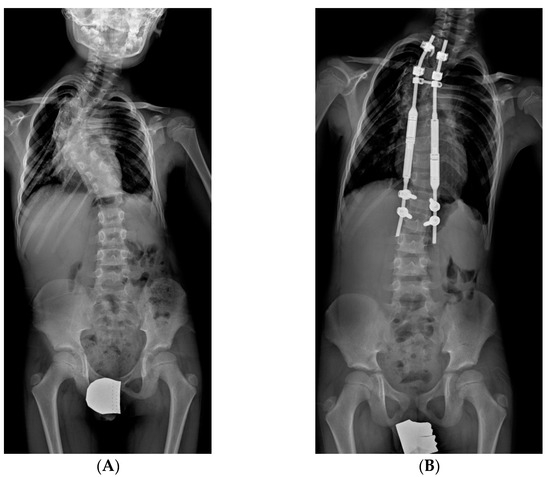

2.3.1. TGR: Traditional Growing Rods

2.3.2. MCGR: Magnetically Controlled Growing Rods

3.2. Curve Correction